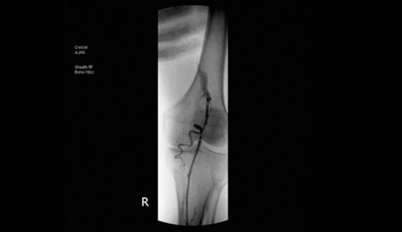

Double guide video of hospital’s original non-surgical varicose vein treatment, ‘ultrasound’ and ‘angiography’.

• Basic diagnostic tool for varicose vein is ultrasound. Doppler’s ultrasound allows to apprehend blood flow rate, area, and regurgitation in color. However, ultrasound test can identify blood circulation and diagnose diseases, but only angiography can visualize overall blood vessels. MONT hospital conducts angiography that can apprehend venous condition in real time with Doppler’s ultrasound simultaneously. The core principle of varicose vein is to identify start and end of the problematic vein and give an appropriate treatment. This is the key factor in deciding success and recurrence.

• Doppler’s ultrasound that can measure blood circulation velocity, area, and regurgitation.

• Angiography that can visualize overall vascular condition. It clearly identifies start and the end of problematic lood vessel to increase success of the treatment